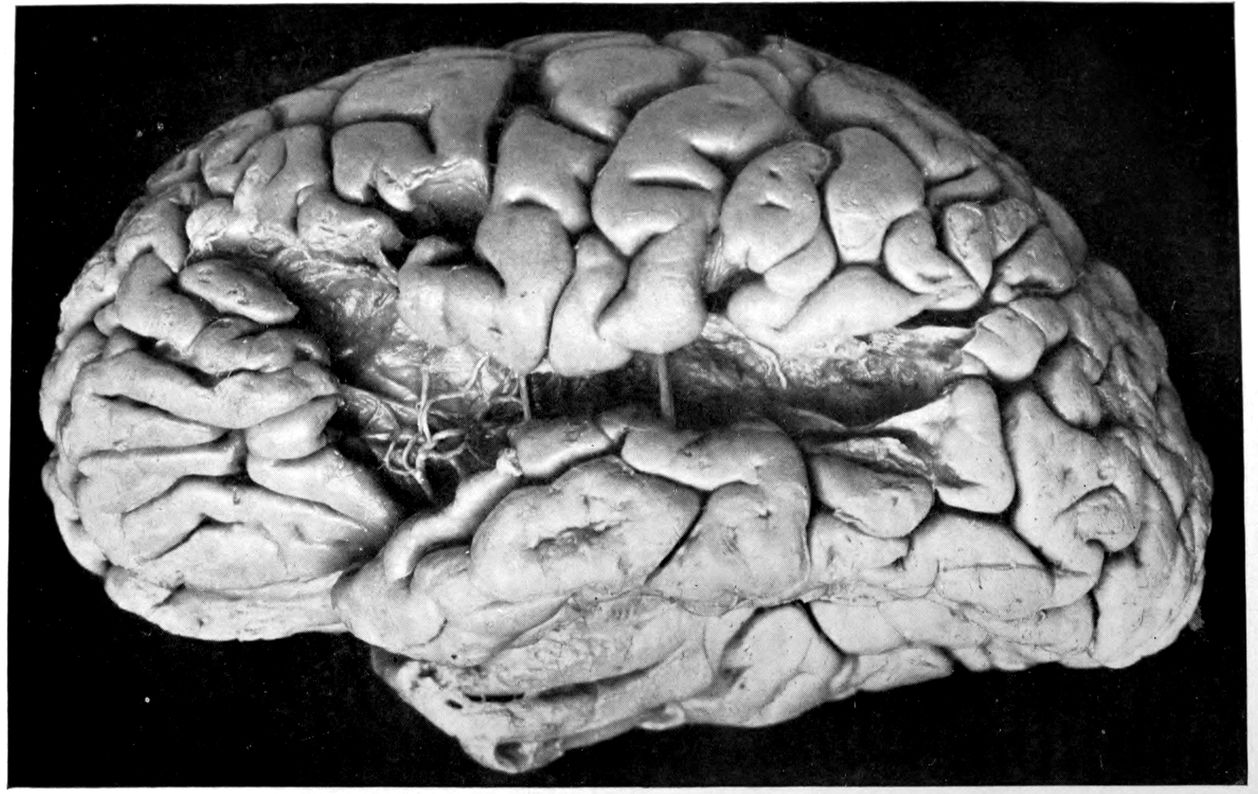

The brain post mortem showed severe atheromatous degeneration of the arteries at the base of the brain. Both middle cerebral arteries showed scattered atheromatous patches. The pia mater was transparent and delicate, except in the regions of both Sylvian fissures. There were residuals of old softening in both temporal lobes. In the fresh brain the regions of the right and left first temporal convolutions were sunken inward, and the pia intimately adherent to the 36softened areas. The limits and more exact localizing of these softenings were worked out from serial sections.

Head: Calvarium of moderate thickness; diploë present; dura slightly adherent over bregmatic region. Longitudinal sinus contains cruor clot. Dura is somewhat thickened and slightly more opaque than normal. Pacchionian granulations, small but fairly numerous. Pia contains throughout a considerable excess of clear 44serous fluid. The convolutions in general are of good breadth and proportion. There is an atrophic area roughly circular in outline and about 2 cm. in diameter in the posterior part of the right third frontal convolution corresponding to Broca’s area on the opposite hemisphere. The space thus formed is filled with edema held by the pia. On the left side is a similar subpial collection which covers the site of the posterior portions of all of the third frontal convolutions, parts of the lower end of the precentral convolution, and the whole of the first temporal convolution, which have disappeared entirely. The basal vessels show slight changes.

Summary: Here is a picture made up almost purely of Vascular Neurosyphilis, with Secondary Spinal (Pyramidal Tract) Changes. Doubtless the genesis of this picture is allied to that of Case 1 (Alice Morton) and to that of the terminal vascular complications in a tabetic, Case 2 (Francis Garfield).

The absence of meningeal and parenchymatous (i.e., outside the region of necrosis produced by the vascular disease) lesions is characteristic of an important group of neurosyphilitic diseases. It is clear that the case, although one of extensive lesions, is not one of diffuse lesions in the sense of Case 1 (Alice Morton).

Vascular neurosyphilis—effects of syphilitic thrombosis of Sylvian artery 10 years before death. (Case 4.)